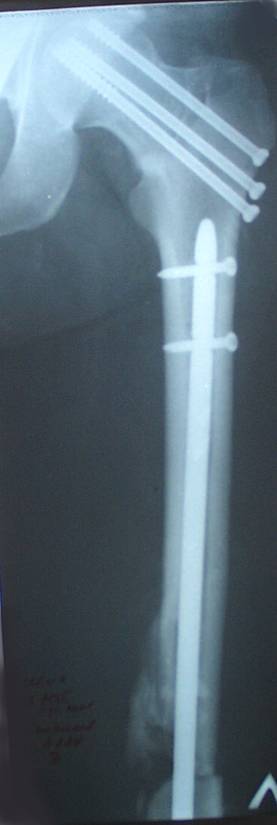

Уважаемый Сергей, избрав вариант DHS плюс ретроградный гвоздь Вы явно обезопасите себя от проблем, связанных с введением штифта через trochanteric fossa. Очень это может быть проблематично, Вы правы. Поэтому DHS плюс ретроградный гвоздь - спокойно выполнимый вариант, особенно в "чужом" отделении. Схожий свой случай из далёкого теперь уже 1999г. прилагаю, только вместо канюлированных винтов у Вас будет DHS (VHS). А если антеградный гвоздь - то только из тех, что предназначены к введению через верхушку вертела. И это тоже выполнимо, но сложнее. Мне так кажется.